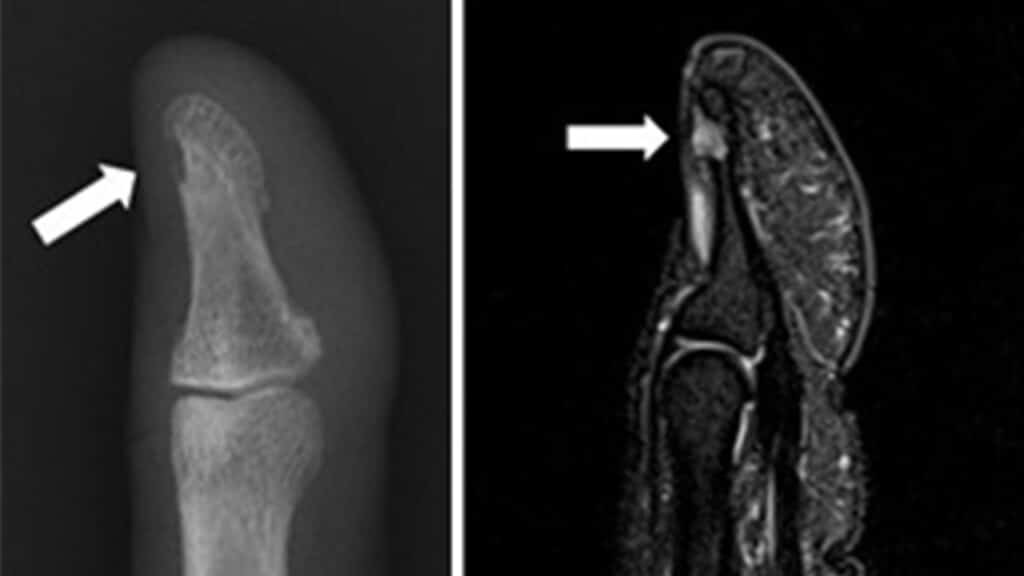

고통을 참다 결국 병원을 방문한 여성은 병원에서 정밀 검사를 받게 됩니다. MRI 검사 결과 그녀의 손톱 밑에는 작은 종양이 자리 잡고 있었는데요.

크기 2mm의 작은 종양이 지속적인 고통의 원인이었던 것입니다. 원인을 알게 된 후 수술을 위해 손톱을 잘라내고 종양을 제거하였습니다. 수술이 끝난 후 그녀는 손톱에서 더 이상 통증이 느껴지지 않았다고 합니다.

해당 사연의 주인공 손톱 속 종양은 ‘사구체 종양(Glomus tumor)’이라 불리는 종양으로 피부 어디 부위에서나 생길 수 있으며 주로 손톱 또는 발톱 밑에서 발생된다고 합니다.

종양이 있는 부위의 크기가 크다면 손발톱이 갈라지거나 변색이 되는 경우도 있지만, 보통은 육안으로는 쉽게 확인할 수 없는 경우가 많아 초음파 검사로도 발견하기가 어렵고, 종양 발생 후 오랜 기간 방치 시 수지골의 함몰이 동반될 수 있습니다.